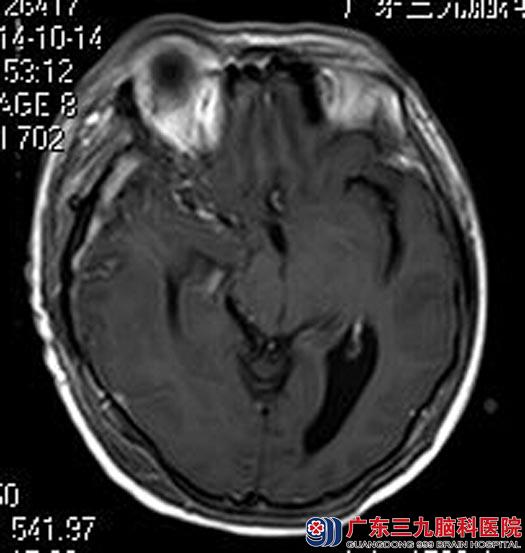

广东三九脑科医院进一步头颅MRI检查结果:右侧额颞部示一不规则形占位性病变,大小约为48.7mm×78.6mm×46.0mm;相应处脑组织明显受压,示大片状脑组织水肿影;右侧侧脑室受压变扁,环池变窄,中脑受压变形,左侧侧脑室轻度扩大,中线结构明显左偏,考虑巨大脑膜瘤,合并大脑镰下疝及右侧海马钩回疝形成。头颅CTA检查提示:右侧额颞部病变内可见少许小血管影,病变边缘可见较多的小血管影。

经会诊讨论:术前予肿瘤部分供血血管栓塞,减少术中出血。后由综合神经外科鲁明主任主刀,在全麻下行右侧额颞部巨大脑膜瘤切除术,术中显微镜下暴露中颅窝,见灰白色肿瘤,质韧,有完整包膜,血供较丰富,予镜下整块全切肿瘤,手术顺利。现朱女士已康复出院。病理结果:脑膜瘤。